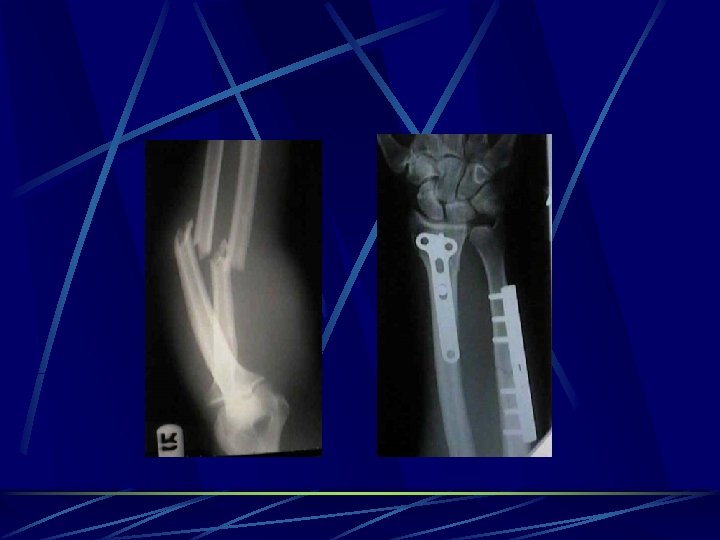

Plates and screws designs vary depending on the anatomic region and size of the bone used in the management of articular fractures allows early ROM and the use of muscles and joints strength and stability, neutralize forces Buttress plates counteract compression and shear - metaphysis and epiphysis used around joints to support intra-articular fractures Compression plates (DCP – Dinamic commpression plate, LC-DCP low contact dinamic commpression plate) counteract bending, shear, and torsion, eccentrically loaded holes in the plate used in long bones (fibula, radius, and ulna) Neutralization plates combination with interfragmentary screw fixation interfragmentary compression screws provide compression, plate neutralizes torsional, bending, and shear forces ( lag screws increases the stability of the construct) (fibula, radius and ulna, and humerus) Bridge plates - management of multifragmented diaphyseal and metaphyseal fractures.

Spetial types of osteosynthesis LISS ( less invasive stabilisation system) implants for MIPPO (minimal invasive percutane plate osteosynthesis) -Herbert´s screw – scafoid # DHS – NOF# basicervical PFN – NOF # pertrochanteric Phillos –prox. humerus DCS (dinamic condylar screw) and DFN (distal femoral nail) - dist. femur Pilon plate – dist. tibia